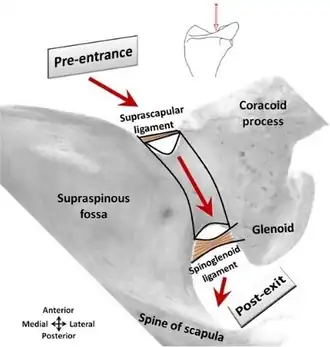

The back of the scapula (also called the dorsal or posterior surface) is arched from above downward, and is subdivided into two unequal parts by the spine of the scapula. The portion above the spine is called the supraspinous fossa, and that below it the infraspinous fossa. The two fossae are connected by the spinoglenoid notch, situated lateral to the root of the spine.

- The supraspinous fossa, above the spine of scapula, is concave, smooth, and broader at its vertebral than at its humeral end; its medial two-thirds give origin to the Supraspinatus. At its lateral surface resides the spinoglenoid fossa which is situated by the medial margin of the glenoid. The spinoglenoid fossa houses the suprascapular canal which forms a connecting passage between the suprascapular notch and the spinoglenoid notch conveying the suprascapular nerve and vessels.[4]

- At its lateral part is a deep, semicircular notch, the scapular notch, formed partly by the base of the coracoid process. This notch is converted into a foramen by the superior transverse scapular ligament, and serves for the passage of the suprascapular nerve; sometimes the ligament is ossified.

Suprascapular canal path

Suprascapular canal path -